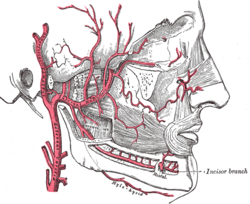

Mylohyoid branch of inferior alveolar artery

| Mylohyoid branch of inferior alveolar artery | |

As the inferior alveolar artery enters the mandibular foramen, it gives off a mylohyoid branch which runs in the mylohyoid groove, and supplies the mylohyoid muscle.